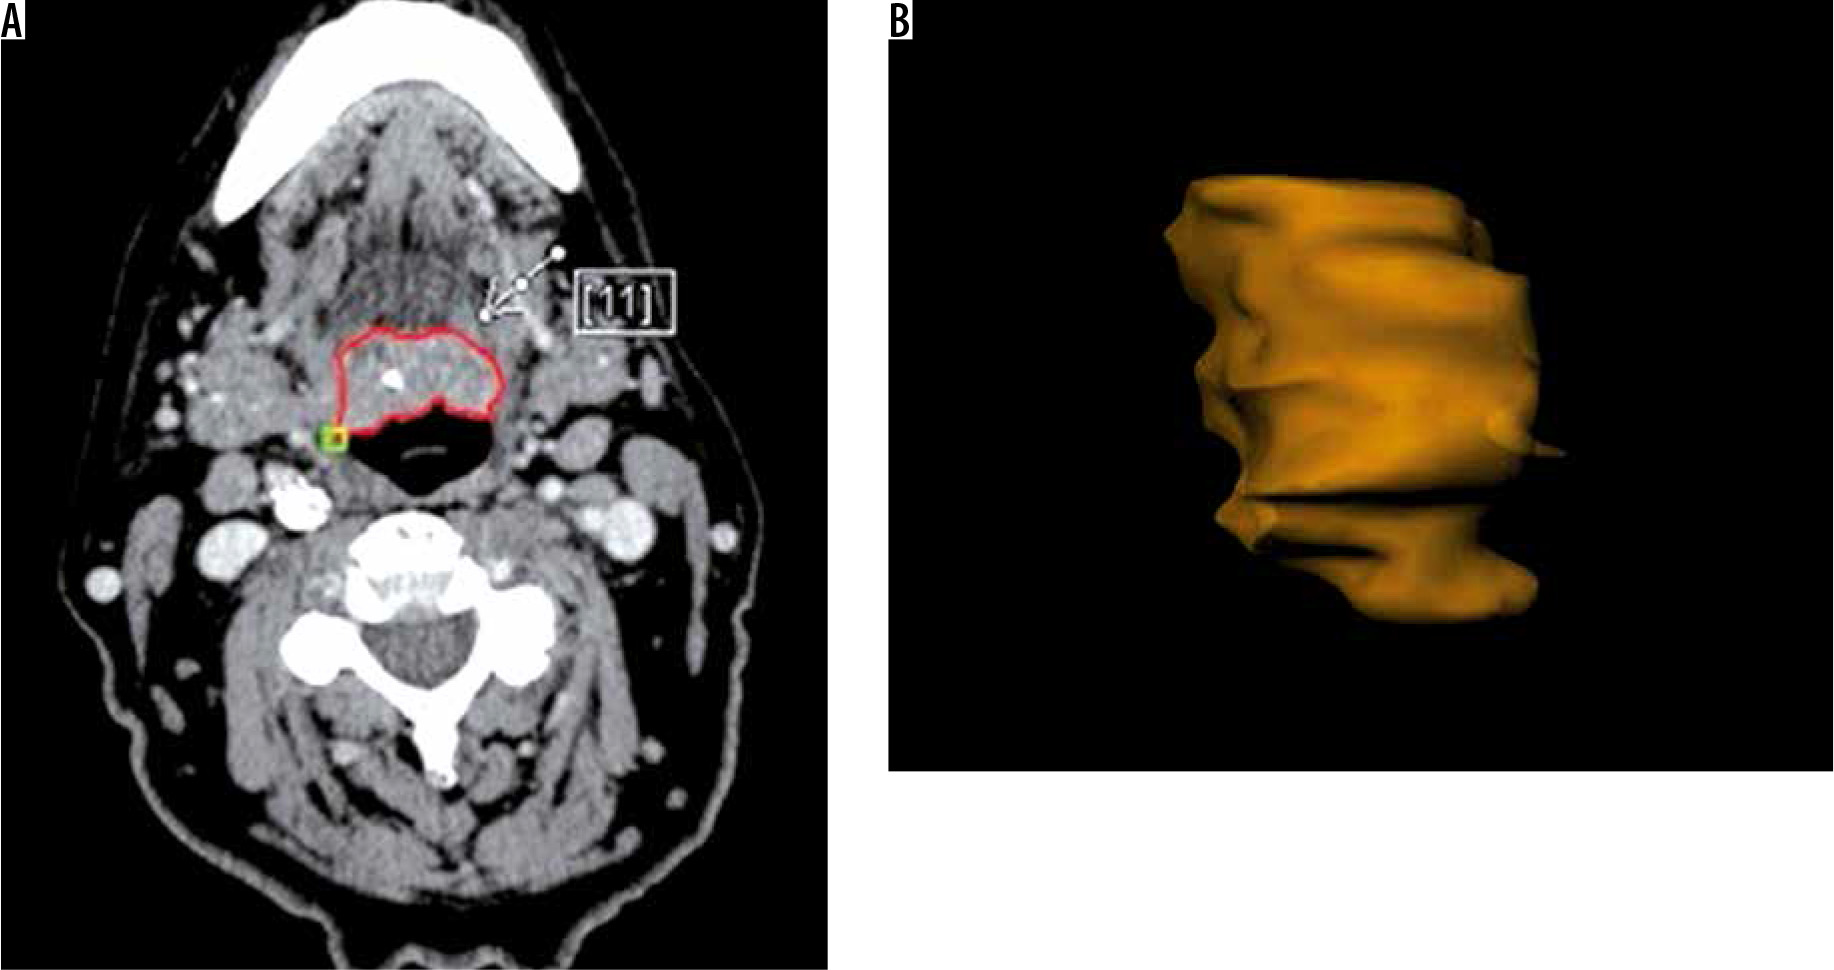

One radiologist calculated the TV manually measuring tumour length (L) and width (W) on the axial plane (Figure 1) and the height (H) on the sagittal plane (Figure 2). Then he calculated the TV using the formula 0.5236 × L × W × H (ellipsoid formula: volume = length × width × height × 0.5236) [9]. The other radiologist used syngo.CT-Liver-Analysis software to calculate the TV by contouring the volume only on axial CT images (Figure 3A). The advantage of this method is that a 3D model of the tumour is obtained (Figure 3B). Both volume-measuring methods were compared with the results of GTV-contouring method using 3D ProSoma software (MedCom, Darmstadt, Germany). In our radiotherapy department we use this software for organs at risk (OARs) contouring. We can build more treatment plans, and faster, and have more time to focus on delineation of GTVs and more time for our patients. The program allows the identification and contouring of the target volume and the creation of the clinical target volume (CTV). We also compared the times of the two methods: the first radiologist who used the simple formula needed on average one minute to determine the volume, while the second radiologist needed between three and five minutes with the syngo.via method, depending on the volume. The radiotherapist, on the other hand, needed between 1.5 and 2 minutes per patient with the 3D ProSoma software.